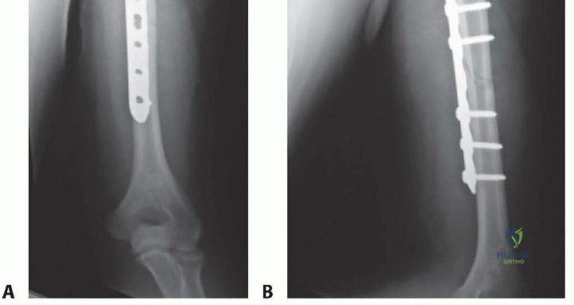

Fracture Reduction and Plate Fixation

Once the fracture site is exposed and the hematoma evacuated, reduction is achieved using longitudinal traction, rotation, and direct manipulation with bone reduction forceps. Soft tissue interposition, particularly from the brachialis or triceps, must be cleared from the fracture ends.

For simple fracture patterns (transverse or short oblique), absolute stability is the goal. If the obliquity allows, an interfragmentary lag screw is placed perpendicular to the fracture plane to generate interfragmentary compression. A 4.5 millimeter narrow plate is then contoured to the anterolateral aspect of the humerus. The plate is applied in a neutralization mode. If a lag screw cannot be placed, the plate is applied in a dynamic compression mode utilizing eccentrically drilled screws.

For comminuted or segmental fractures, relative stability is preferred. The fracture zone is bypassed without disturbing the comminuted fragments, preserving the local biology. A longer plate is utilized to span the fracture, acting as a bridge construct. Locking screws are highly beneficial in this scenario, particularly in osteoporotic bone, as they provide angular stability and reduce the risk of hardware pullout.

Clinical & Radiographic Imaging